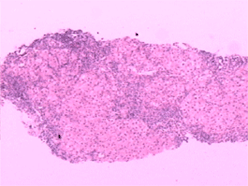

3、組織學特徵:黏膜下靜脈擴張,無或僅有輕微炎性細胞浸潤為其特徵性表現。其他還有黏膜下小動靜脈壁增厚,靜脈動脈化。黏膜橫斷面毛細血管面積較正常增大。胃黏膜毛細血管發育不良,散在裸露於胃腔內,表面無上皮組織覆蓋。胃黏膜小動脈變直,螺鏇度減輕。小血管注射研究發現,黏膜下動靜脈分流廣泛開放,電鏡觀察顯示毛細血管顯著擴張,內皮小孔擴大,血管內皮與基底膜連線不緊密,出現間隔,血管基底膜不連續,毛細血管基膜與上皮細胞基膜之間距離變寬,上皮細胞腫脹變性。紅細胞從破損的上皮處外滲,並出現於上皮間隙之間。因內鏡活檢取材小且表淺,僅有50%的活檢標本病理見有毛細血管擴張。